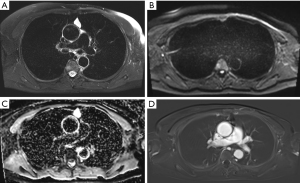

The chest MRI protocol implemented at our hospital is shown in Table 1. The diagnostic MRI criteria for thymic cysts are as follows (Figure 3):

- Well-defined saccular or oval lesions without eccentric wall thickening;

- Signal hyperintensity on T2-weighted images;

- No contrast enhancement on pre- and post-contrast T1-weighted images;

- No diffusion restriction.